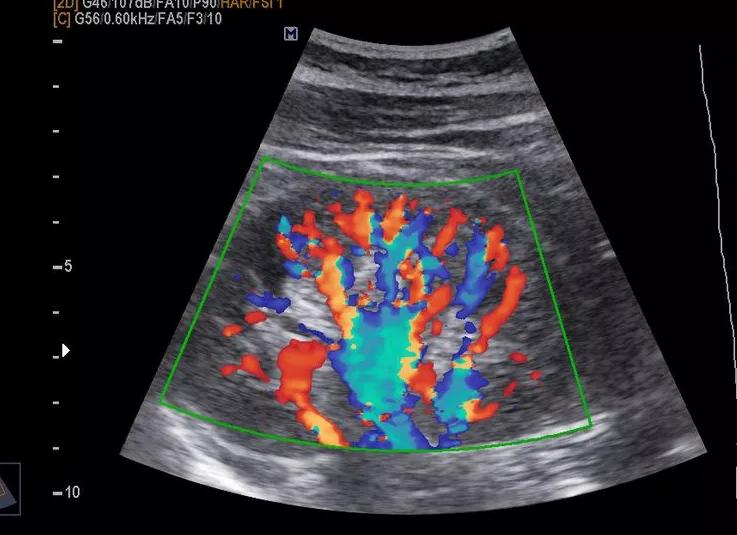

ЦДК можно считать разновидностью классического УЗИ. Основано оно на методе исследования Доплера. Это совокупность обычного УЗИ в черно-белом цвете с применением цветного подсвечивания той или иной области. Цвет позволяет провести оценку кровотока и состояния сосудистой системы.

Черно-белое изображение имеет цветные вкрапления, которые как раз и указывают на скорость и направление кровотока во всех сосудах.

Цветовое допплеровское картирование (ЦДК) – это один из подвидов УЗИ, основанного на эффекте Допплера. Оно также «работает» с оценкой кровотока в сосудах.

В основе данного исследования – совмещение обычного черно-белого УЗИ и допплеровской оценки кровотока.

В режиме ЦДК врач видит на мониторе черно-белое изображение, в определенной (исследуемой) части которого отображаются в цвете данные скорости движения структур.

Так, оттенки красного цвета будут кодировать скорость течения крови, направленного к датчику (чем светлее, тем меньше скорость), оттенки голубого цвета – скорость кровотока, направленного от датчика. Рядом выводится шкала, на которой обозначено, какой именно скорости соответствует тот или иной оттенок. То есть, синим цветом обозначены не вены, а красным – не артерии.

Цветовое допплеровское картирование визуализирует и анализирует:

• направление,

• характер,

• скорость кровотока;

• проходимость,

• сопротивление,

• диаметр сосуда.